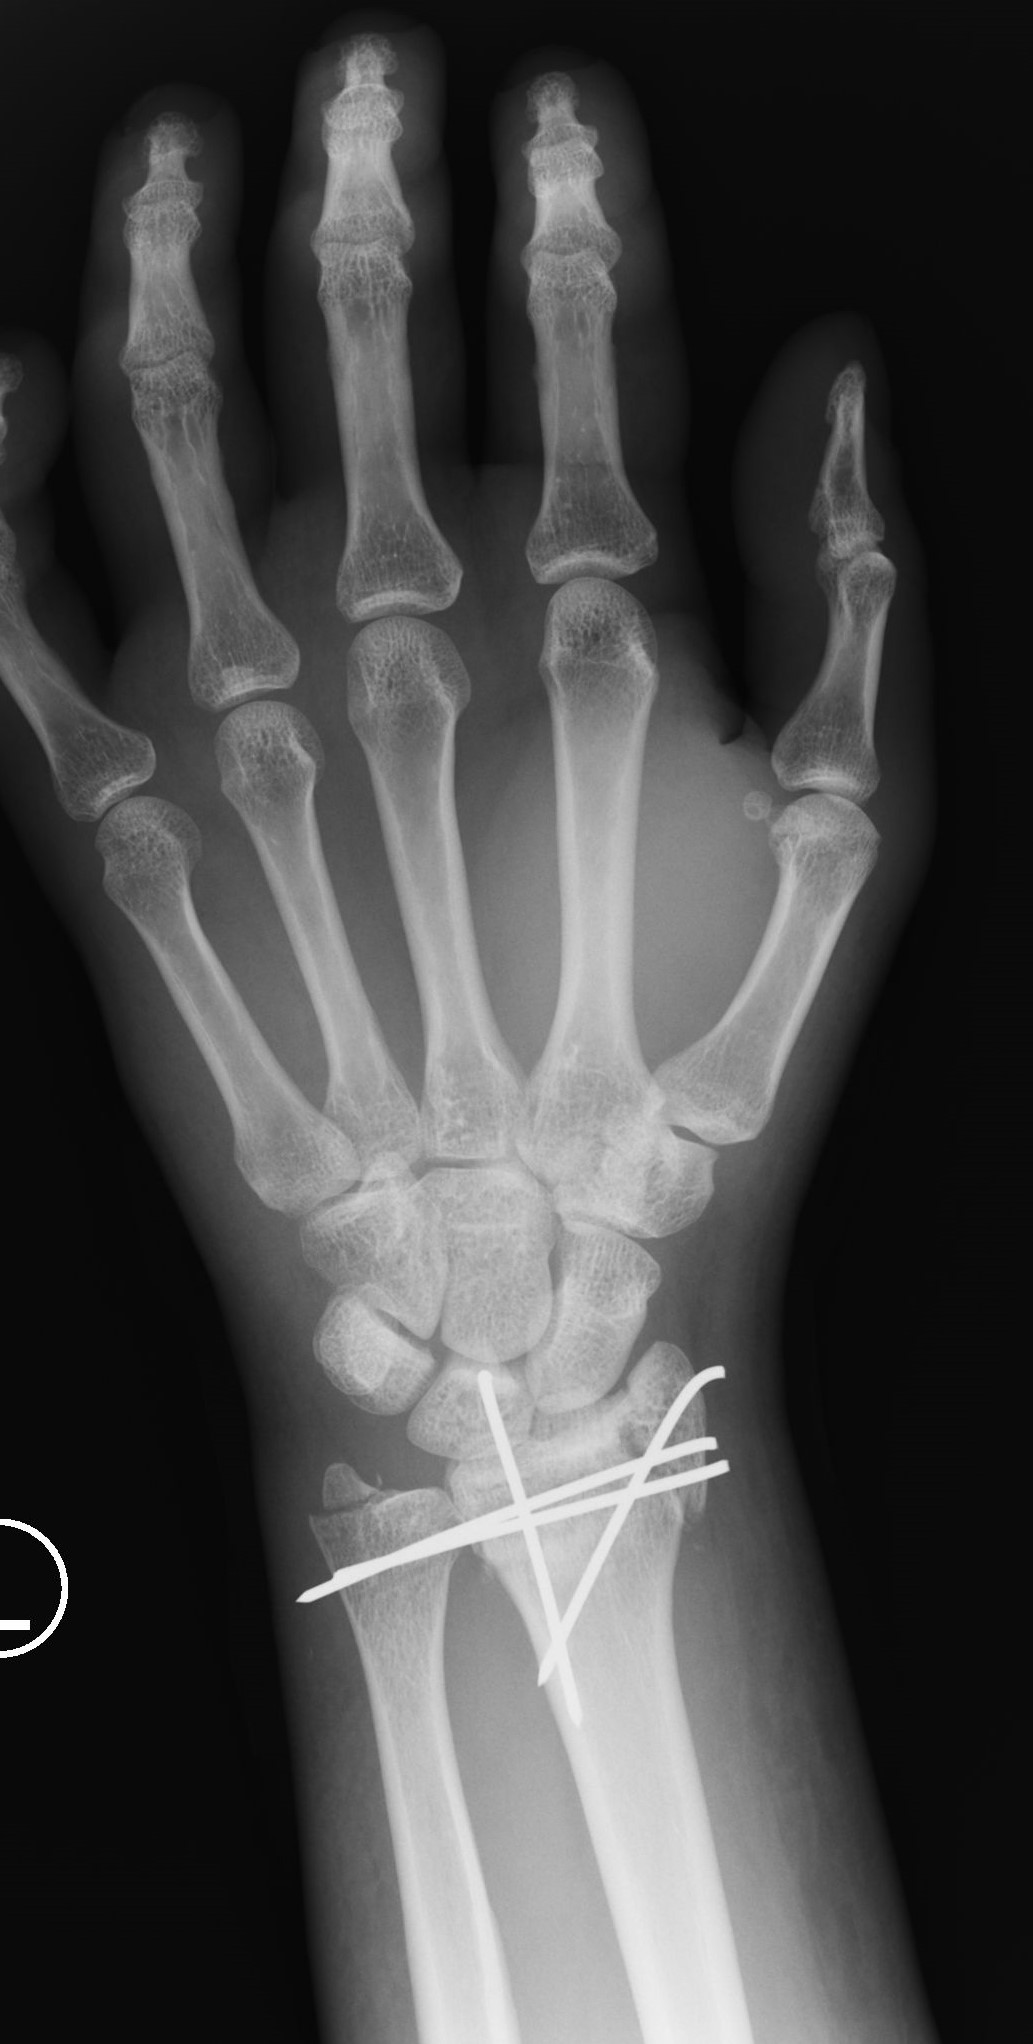

Successful surgery to reduce and fixate with the plate of neglected, displaced fracture of the distal radius

Treatment of neglected, displaced or united distal radial fractures (DRFs) is difficult, because it requires either wedging the almost consolidated fracture and reduction to the correct position, or cutting the united bone and putting it in the correct position (corrective osteotomy). Both treatments are associated with the risk of failure and complications. The paper presents a case of almost fully united DRF in a man, in whom 5 weeks after the injury, and after unsuccessful primary fixation with K-wires, the bone fragments were surgically wedged, aligned and fixed with a palmar plate. The result of treatment after 2 months was satisfactory. Early surgery allowed for a significant shortening of the recovery period and allowed the patient to return to work.